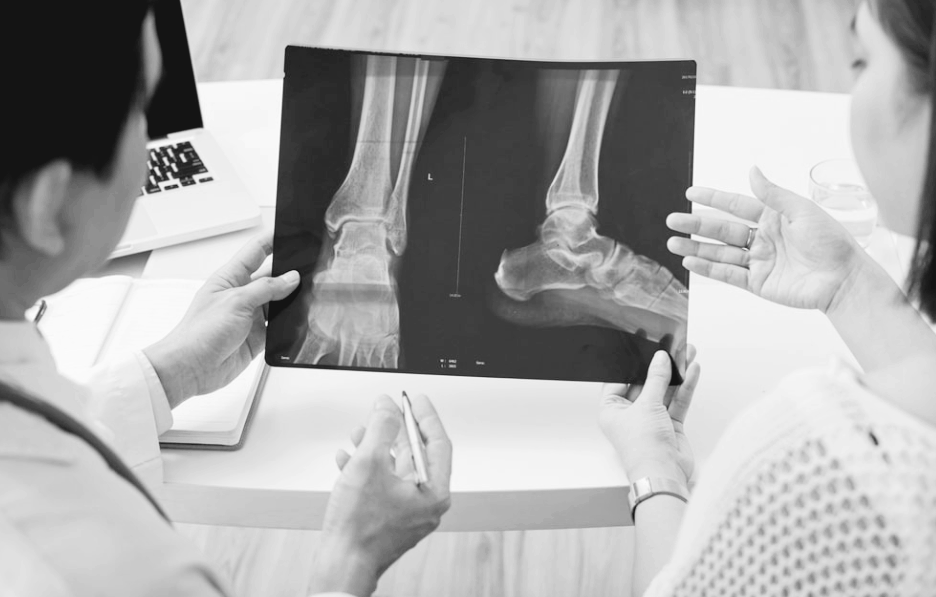

🏥 그리고 의학계를 뒤흔든 혁명

뢴트겐은 이 광선을 'X선(X-ray)'라고 명명했어요.

하지만 실제로 골절된 뼈를 수술 없이 확인할 수 있게 되자...

의학의 판도가 완전히 바뀌었습니다

수술 전 정확한 진단 가능